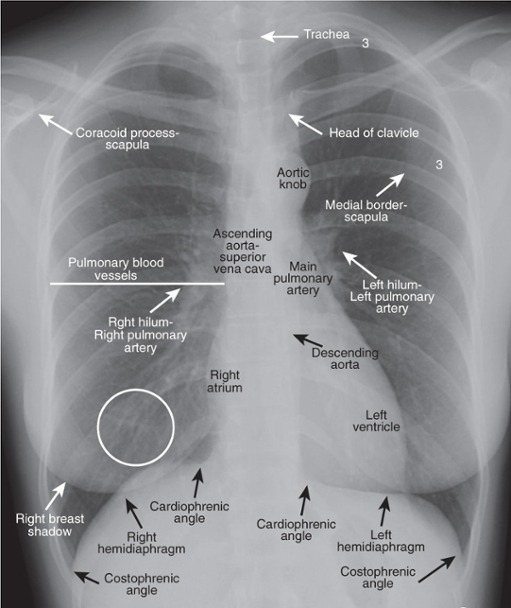

Trachea

A structure seen on chest X-ray that represents the airway.

Hila

Areas on a chest X-ray where the lungs' blood vessels enter and exit.

Diaphragm

The muscle seen on chest X-ray that separates the thoracic and abdominal cavities.

Aortic Knob

The curved appearance of the aorta as seen in chest imaging.

Cardiac Contours

Since we are looking at shadows (knowing the heart is soft tissue density), the silhouette of the heart demonstrates certain contours

Aorta – knob on frontal view

PA – vascular so visible, unlike bronchus; left main sits higher than right

Right and left atria – right atria makes up right heart border; left atria will enlarge superior portion of left heart border

LV – posterior structure; more prominent filling retrocardiac space on lateral

Descending aorta disappears because it is buried in mediastinal soft tissue densities